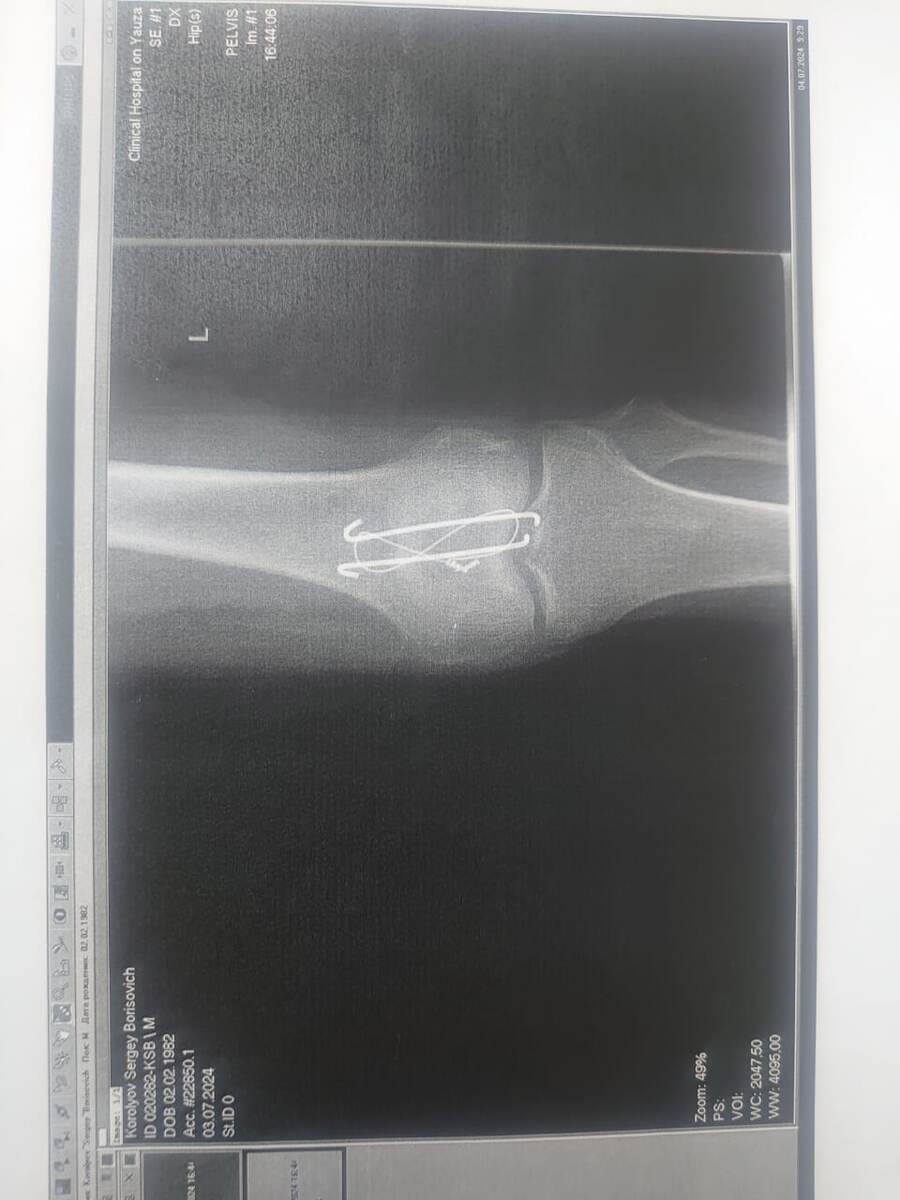

Ещё один пример - методика "массаж поющими чашами" в реабилитации после хирургического вмешательства. Постравматическая сгибательная контрактура коленного сустава. Велосипедная травма. Перелом левого надколенника. Проведена операция: остеосинтез надколенника. Провел 5 сеансов по 10 мин, ежедневно. Ногу распрямил полностью. Такие травмы разрабатывается в среднем 2-3 месяца. Комплексное лечение: механотерапия, кинезиотерапия, имплантные препараты и поющая чаша.